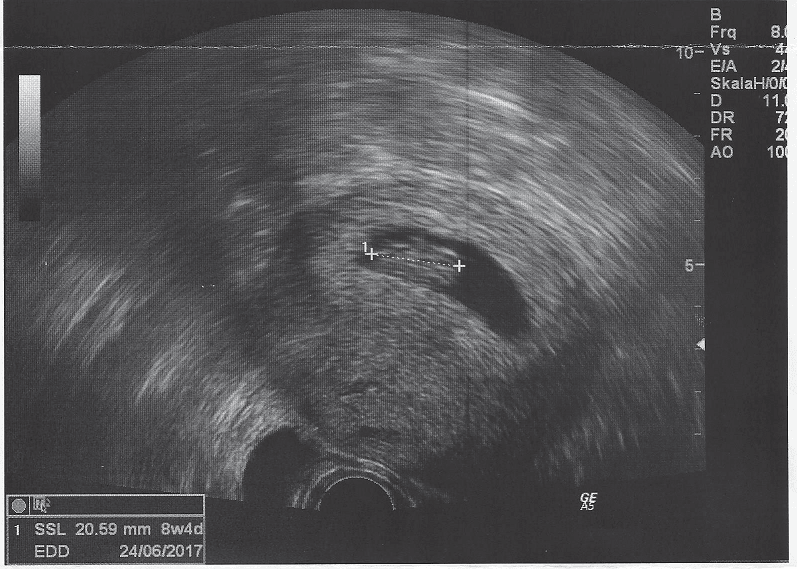

Wszystko jest w najlepszym porządku, Mrówka ma już 20 mm i lekarka jest bardzo zadowolona, dzidzia odpowiada wiekiem dokładnie 8+4. Powiedziała, że ryzyko poronienia wynosi teraz poniżej 5% i wreszcie, wreszcie!, "pozwoliła" nam się cieszyć

Zobacz załącznik 783275